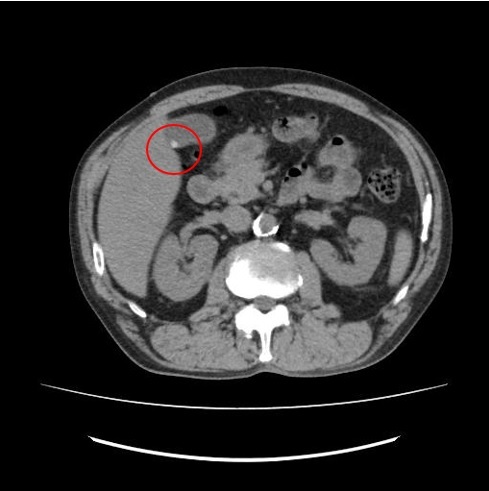

▼CT検査で得られる画像

例5 憩室炎